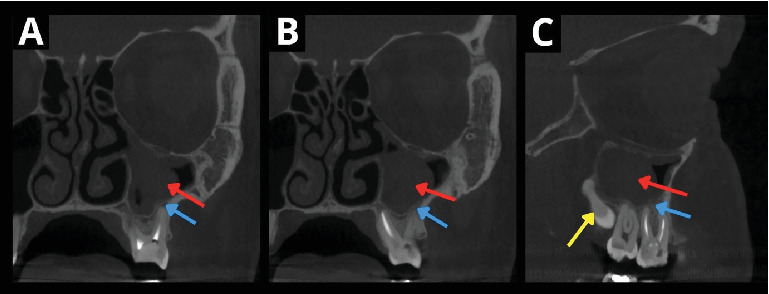

自体牙移植的效果主要取决于移植牙的解剖结构、供牙的类型和牙根形成的发育阶段。成熟牙由于牙髓血运重建潜力较低,并发症发生率较高,需要术前或术后进行根管治疗(RCT)以避免术后并发症,延长了治疗时间和费用。本文报告了一位39岁的患者在根管再治疗失败后,自体移植一颗成熟的智齿来代替第一磨牙。在手术中,移植的牙齿在放置之前进行了口外根切除,以避免需要提升施耐德膜,在手术切除上颌窦囊性病变后,施耐德膜显示不完全愈合。术前和术后均未进行随机对照试验。在3年的随访中,牙齿无症状。使用标准的活力测试难以确定自体移植牙的活力,这取决于患者的主观反应,但使用脉搏血氧仪客观地证实了这一点。本病例不仅显示了老年患者成熟牙移植血运重建的可能性,也为如何客观地确认和测量自移植牙的血运重建提供了可能的术后方案。

The outcome of tooth autotransplantation depends mainly on the transplant tooth's anatomy-the type of donor tooth and the developmental stage of root formation. Mature teeth display a higher complication rate due to lower pulp revascularization potential, requiring root canal treatment (RCT) pre- or postoperatively to avoid postoperative complications, which extends treatment duration and cost. This report details a 39-year-old patient's autotransplantation of a mature wisdom tooth to replace the first molar after unsuccessful root canal retreatment. During the surgery, an extraoral root resection of the transplanted tooth was performed prior to placement to avoid the need to elevate the Schneiderian membrane, which displayed imperfect healing following the surgical removal of a cystic lesion in the maxillary sinus. RCT was not performed before nor after the procedure. At the 3-year follow-up, the tooth was asymptomatic. The vitality of the autotransplanted tooth was difficult to determine using standard vitality tests, which depend on patients' subjective responses, but the use of pulse oximetry objectively confirmed this. This case not only shows the possibility of a mature tooth transplant revascularization in an older patient but also gives a possible postoperative protocol of how to objectively confirm and measure the revascularization of the autotransplanted tooth.